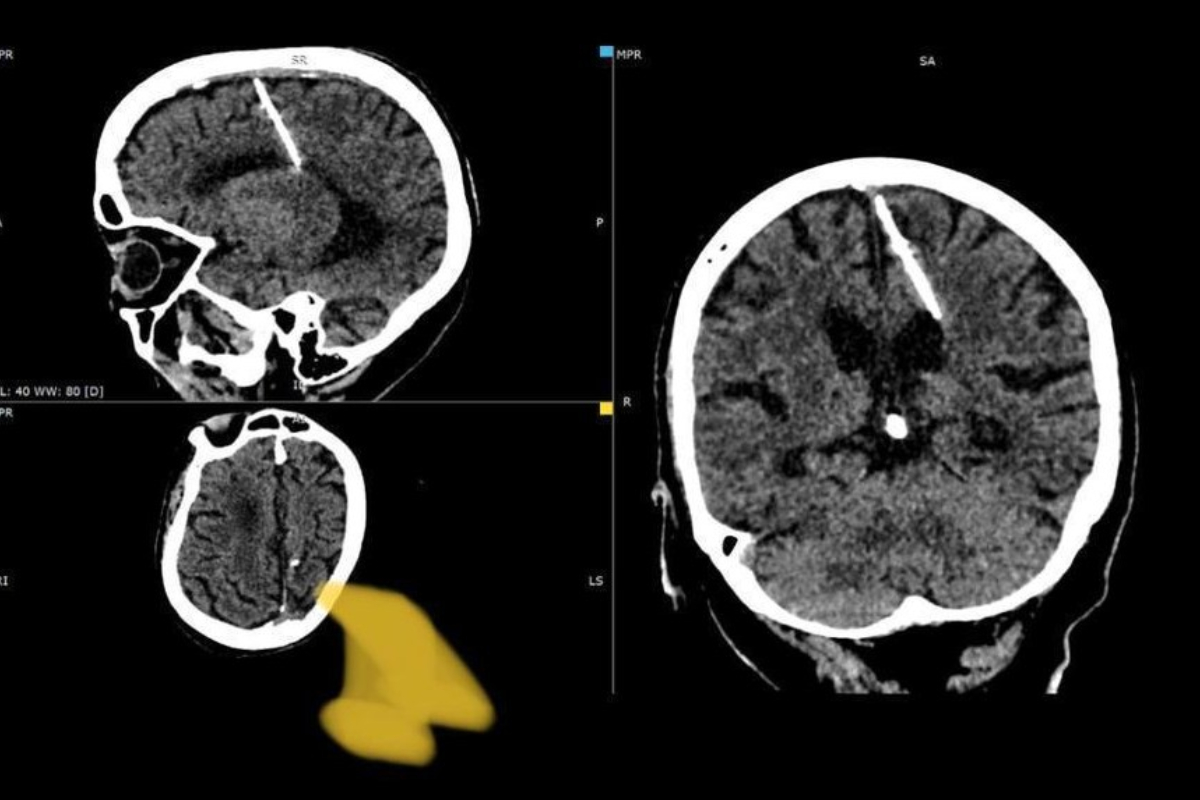

Russian doctors discover needle in woman’s brain in Sakhalin

Russian doctors discovered a needle in a woman’s brain in Sakhalin. This unexpected discovery came to light during a CT scan. Such cases were not uncommon during periods of famine. A startling revelation emerged as Russian doctors discovered a one-inch-long needle inside the brain of an 80-year-old woman residing in Russia’s Far East. This unexpected … Read more